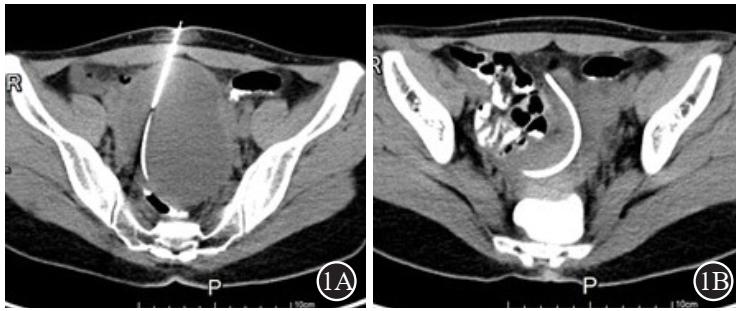

本研究团队通过 CT 精准引导,经皮穿刺留置多侧孔猪尾型引流管,可以更加充分有效抽吸、冲洗囊腔,并可安全、多次注射泡沫硬化剂治疗,更加彻底硬化治疗囊壁,有效粘闭囊壁从而显著提高疗效(整体有效率为 98.0%),同时有效避免囊液及硬化剂外渗风险,显著提高治疗安全性。

经前腹壁穿刺置管硬化治疗

经骶尾部穿刺置管硬化治疗